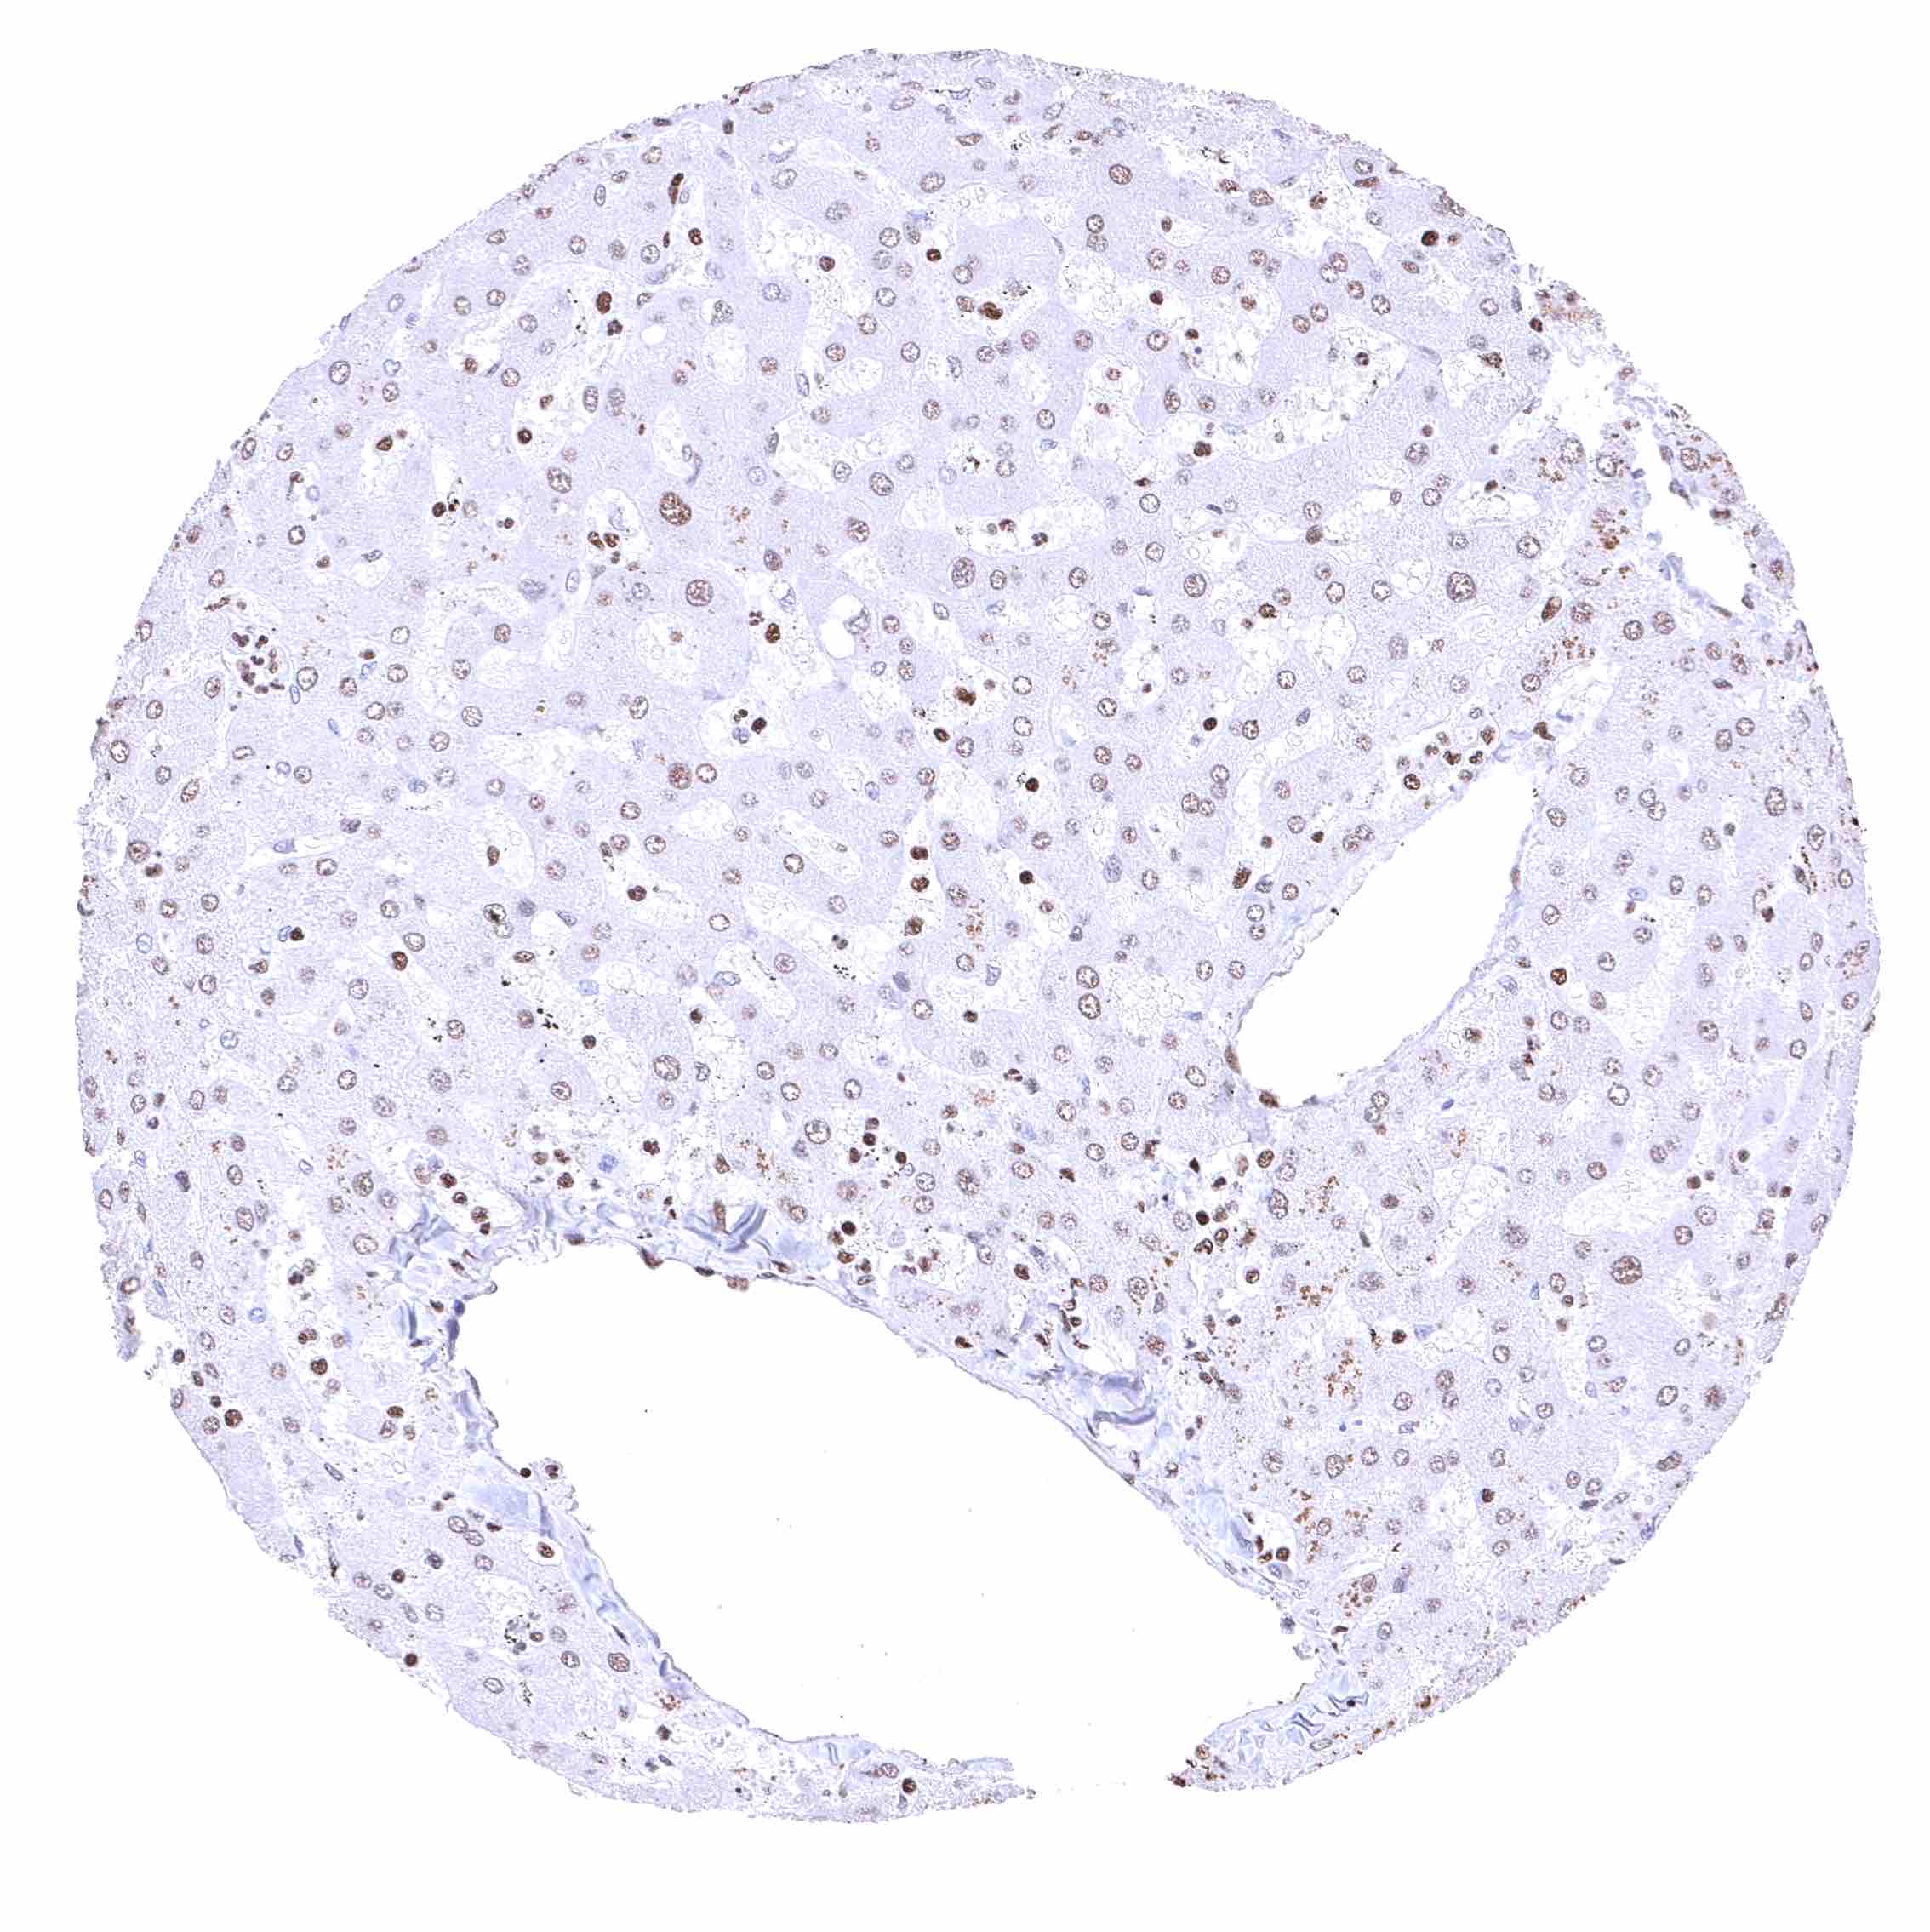

Liver – Nuclear BRD4 staining occurs in all cells, but is clearly weakest in hepatocytes.